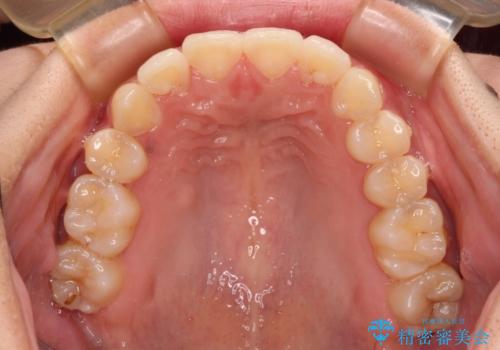

八重歯の抜歯矯正 補助装置とワイヤーを併用したインビザライン矯正治療

- 八重歯と上顎正中のズレを気にして来院された患者様です。

インビザラインによる矯正治療を希望されたため、八重歯改善のための抜歯矯正部分や上顎正中の大幅に位置移動は、補助装置やワイヤー矯正を併用し、その後はインビザラインにて行うこととしました。

骨格的に下顎が左側に変位していたため、上下正中を合わせることは困難であることは分かっていましたが、可能な限り合わせることができました。